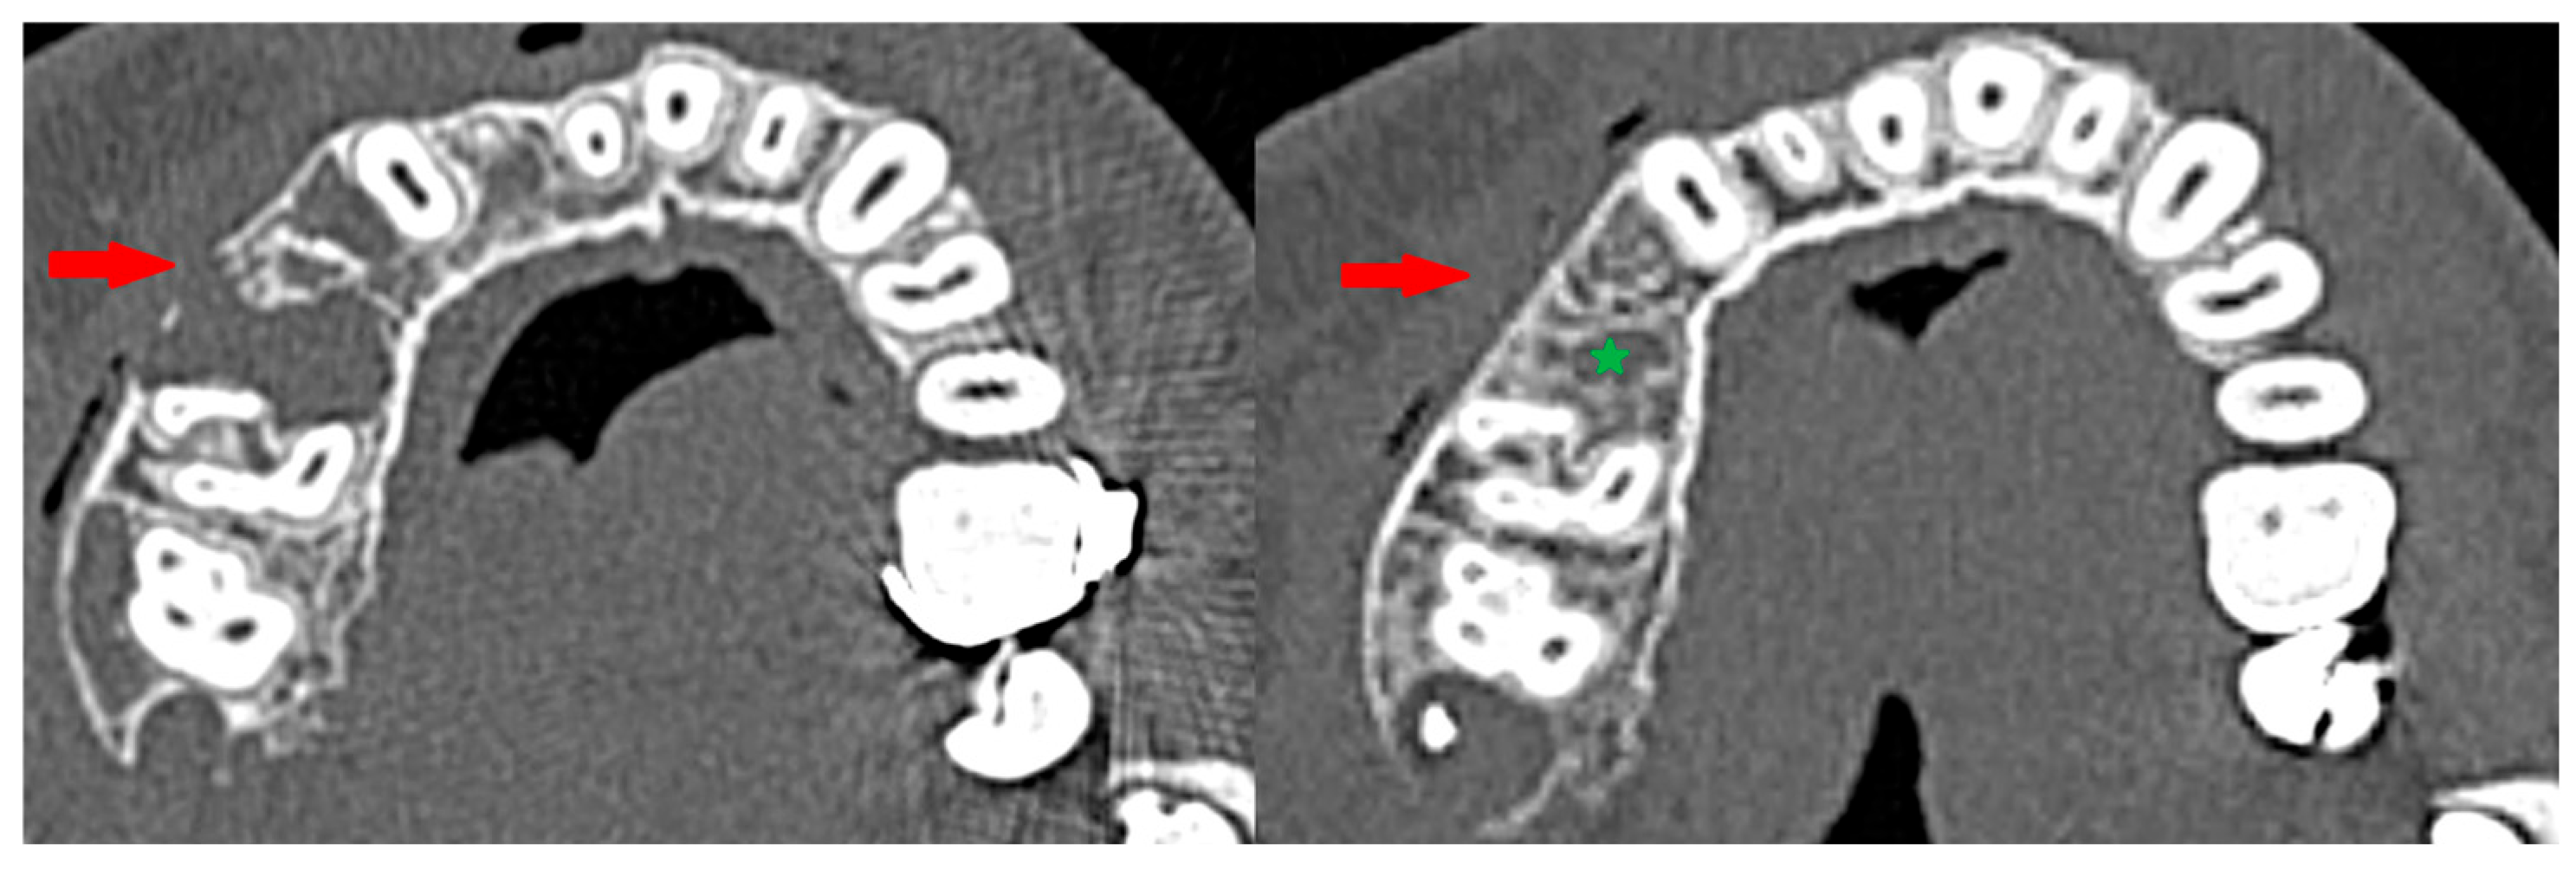

1. Introduction

3. Results

3.3. Osteosclerotic Rim (Peripheral Corticalization)

3.5. Recurrence